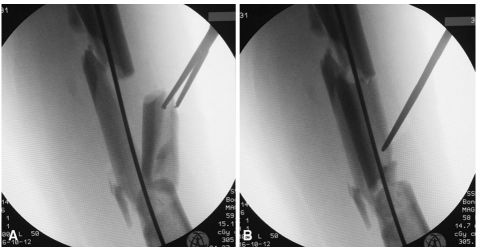

牵引后,将足部置于中立或轻微外旋位置,在正位和侧位通过透视评价骨折位置/复位。如果复位被认为是可以接受的,外科医生可以继续进行皮肤消毒和铺单;如果不能接受复位,通常远端骨折块处于向后移位状态;在这种情况下,为了便于复位和接骨,可以在远端骨折块下方放置拐杖,以抬起骨折块并获得远近端骨折对位(如图1A-C所示)。如果观察到水平的骨盆倾斜增加了近端骨折块的外旋,外科医生应该在术侧臀部下面放置沙袋或布单来纠正。

图1 A拐杖位于远端骨折块下方,便于年轻患者股骨粗隆下粉碎性骨折的复位;B股骨粗隆下骨折长髓内钉远端锁定的侧位片;C股骨粗隆下骨折长髓内钉远端锁定的正位片